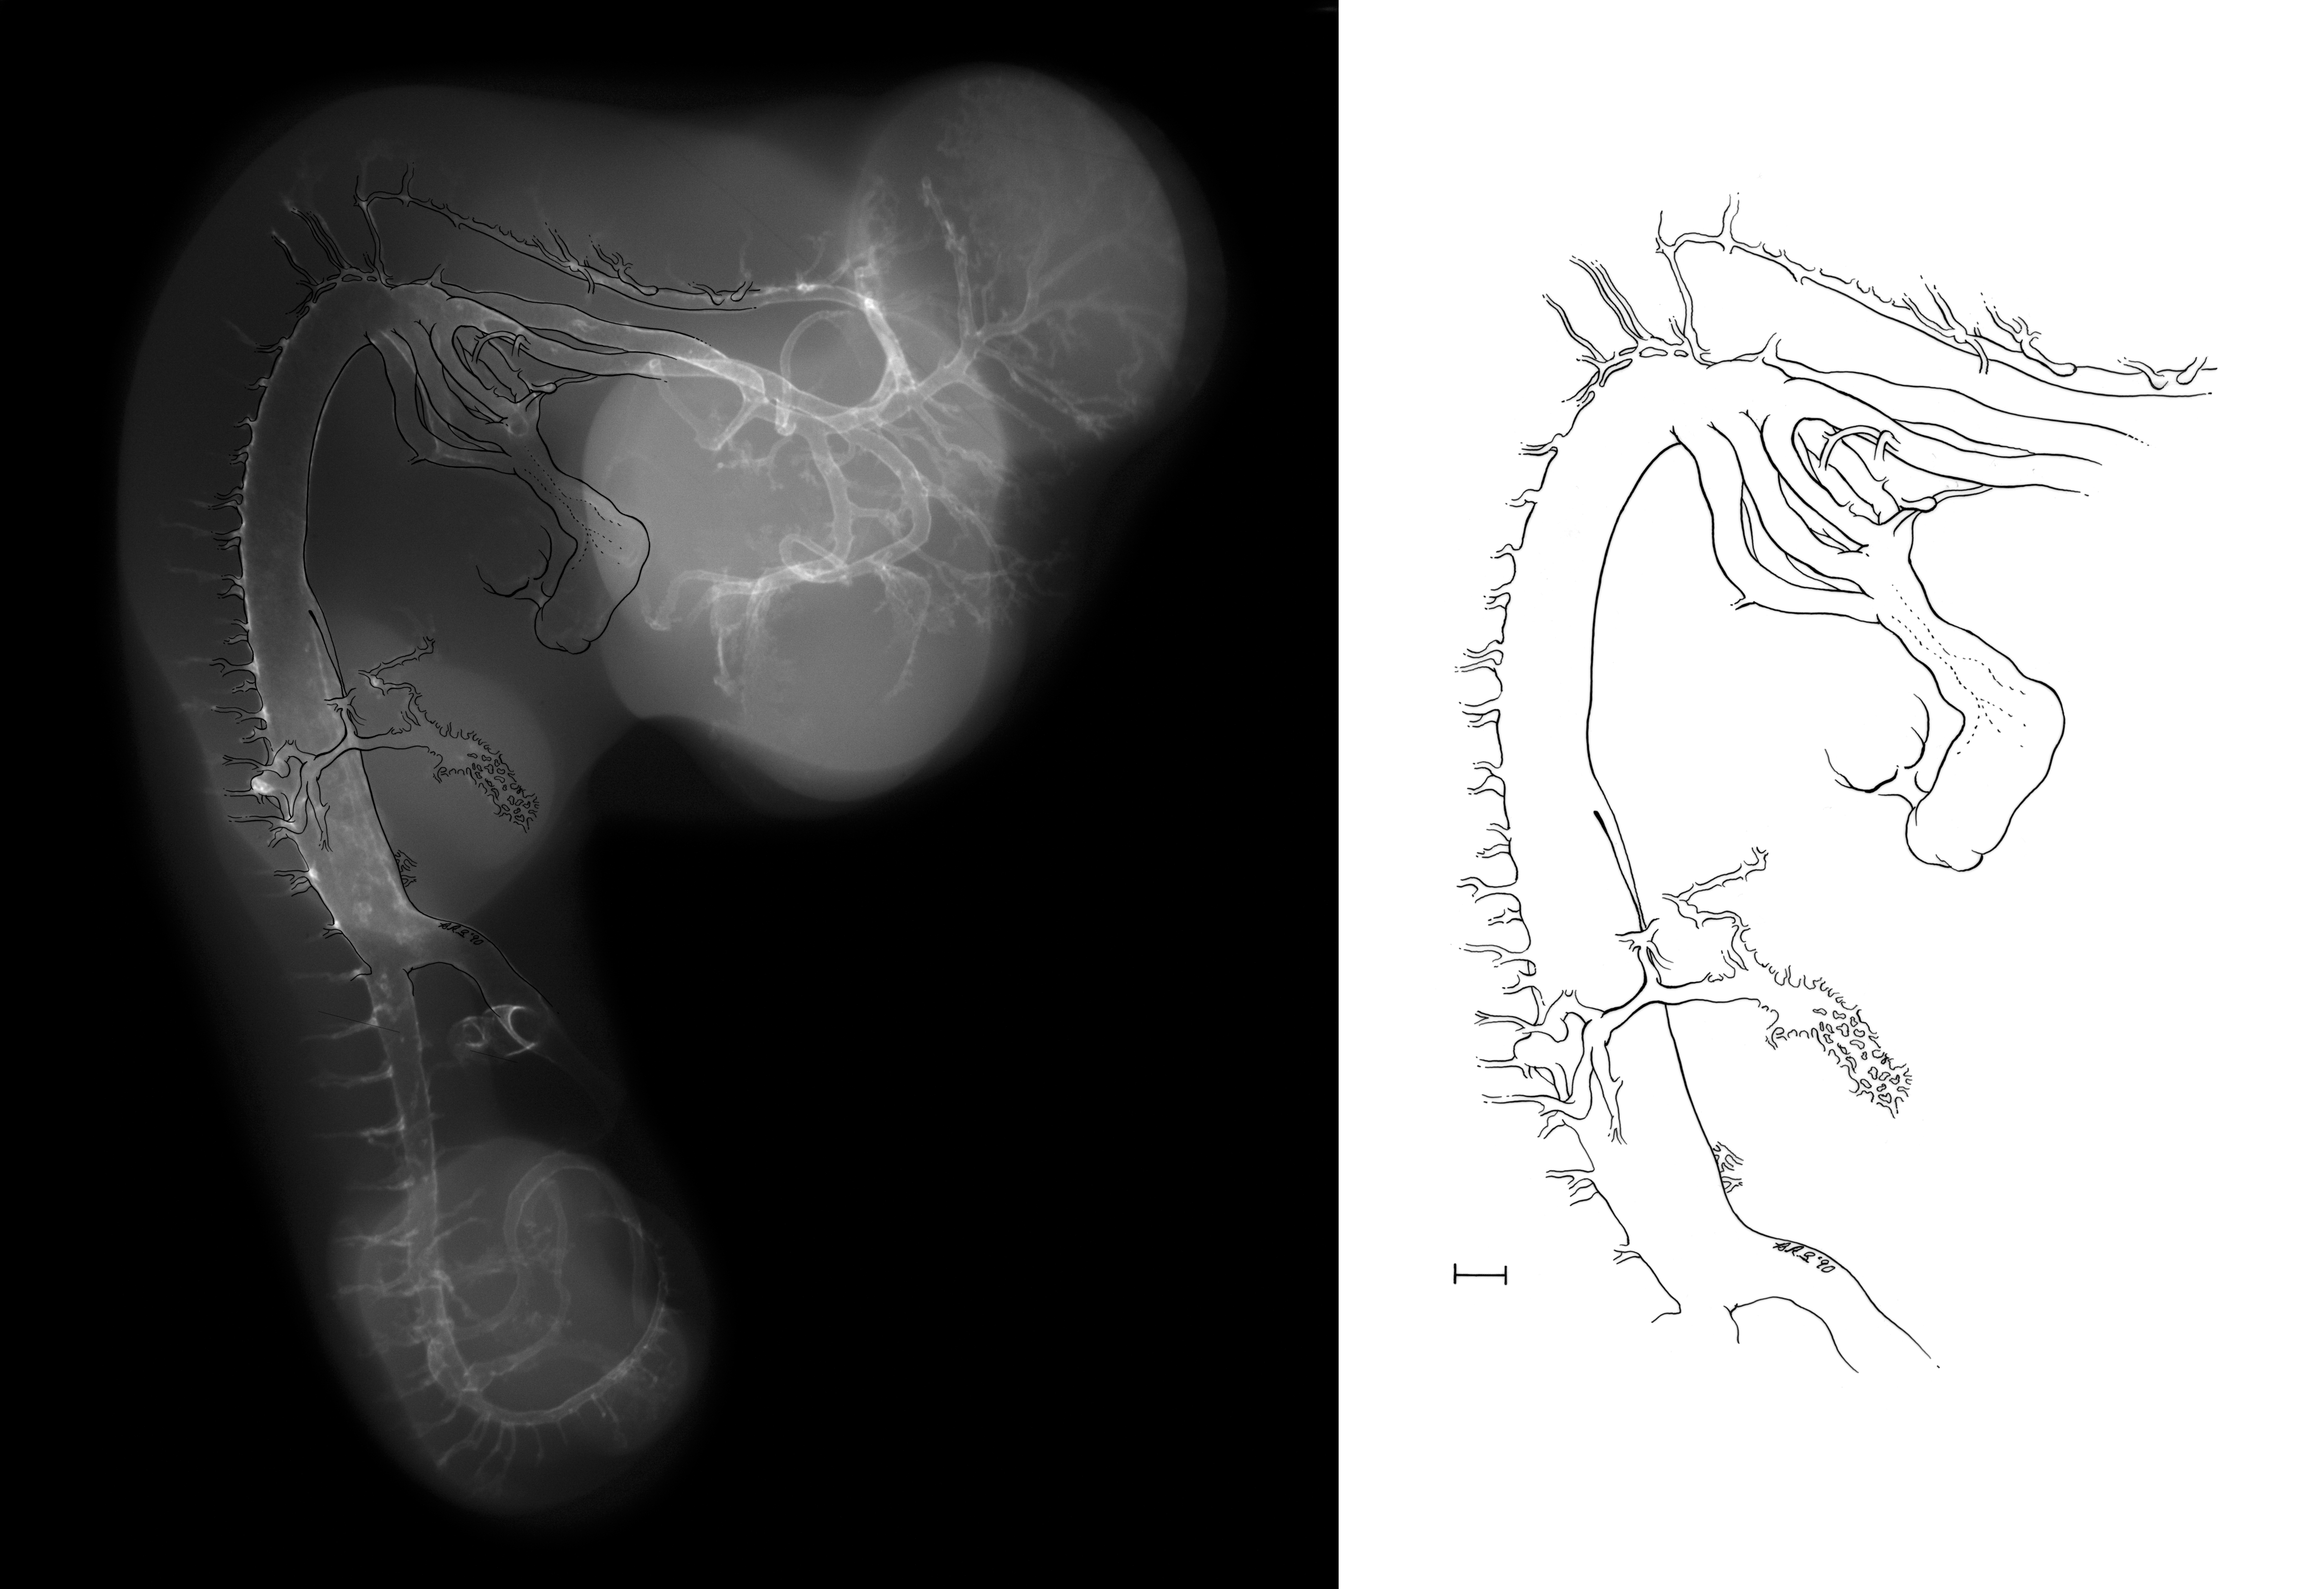

Chick Embryo Microangiography

Hamburger-Hamilton (HH) Stage 25 (approx. 4.5 - 5 days)

X-Ray Micrographs

Drawing